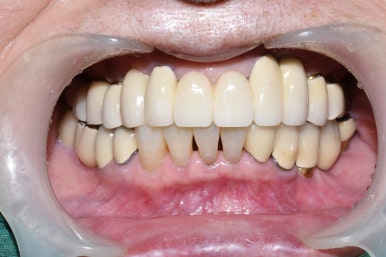

임플란트 완성

치료 후 사진: 일부 임플란트가 보이는 상태

어금니 임플란트 완성 및 임플란트 치료중 사진 (왼) / 완성 후 사진(오른쪽)

어금니 임플란트가 완성된 모습(왼쪽) 및 앞니 임플란트 진행중인 사진과

완성된 사진

기존의 다른 치아와 다른 임플란트, 보철물과 조화를 이루는 앞니 임플란트

완성된 입안에서의 모습 사진입니다.

화살표 표시한 부분내의 치아가 이번에 진행한 임플란트입니다.